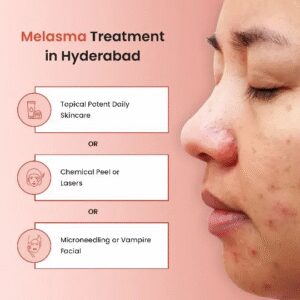

Melasma is a common skin condition that causes brown or gray-brown patches, typically on the […]